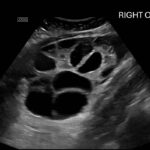

Ovarian hyperstimulation syndrome (OHSS) is a potentially life-threatening complication of assisted reproductive technology (ART). Here, we present the case report of a 30-year-old female undergoing infertility treatment who presented to the emergency department (ED) with nausea and vomiting, abdominal distention, and shortness of breath. On physical exam, she had notable ascites. Computed tomography (CT) of the abdomen and pelvis and pelvic ultrasound (US) revealed significant ascites and enlarged ovaries with multiple cysts. She was diagnosed with severe OHSS and admitted to obstetrics and gynecology (OBGYN) service for five days where she underwent intravenous (IV) hydration and paracentesis. This case report reviews the clinical presentation, categorization, management, and prevention of OHSS and provides examples of imaging findings consistent with the condition.